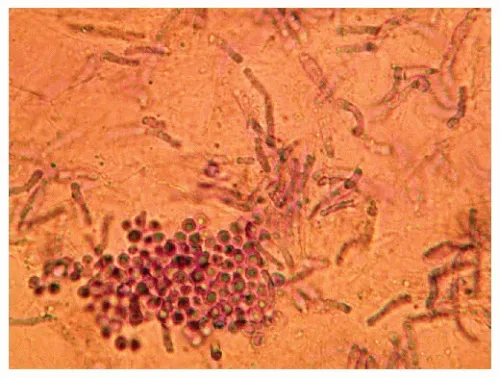

- Dermatophytes (Trichophyton, Microsporum, Epidermophyton)

- Clinical: Tinea corporis (ringworm), tinea pedis (athlete's foot), tinea cruris (jock itch).

- Agents: Allylamines (Terbinafine, Naftifine) are highly effective. Azoles (Clotrimazole, Miconazole) are also common first-line choices. Butenafine is another option.

- Candida albicans

- Clinical: Intertrigo (skin folds), diaper dermatitis, mild oropharyngeal candidiasis (thrush).

- Agents: Nystatin suspension/cream (a polyene, specific for Candida). Topical Azoles are also effective.

- Malassezia spp. (formerly Pityrosporum)

- Clinical: Tinea versicolor (hypo/hyperpigmented macules), seborrheic dermatitis.

- Agents: Selenium sulfide, Ketoconazole shampoo, zinc pyrithione.